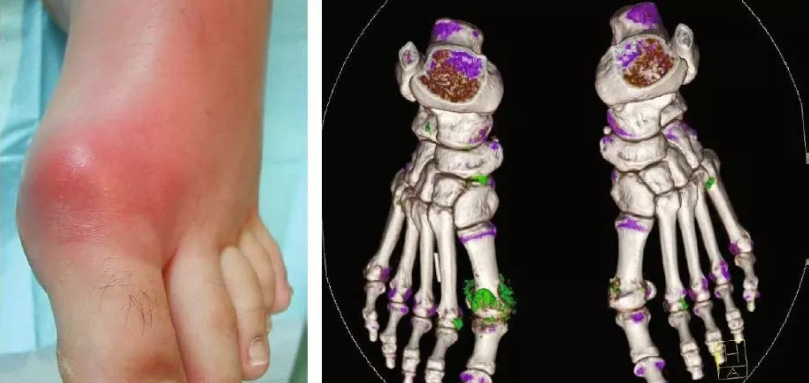

尿酸是人体代谢嘌呤的产物,它具有维持血压、抗氧化应激等作用,但尿酸并不是越多越好。嘌呤代谢紊乱或尿酸排泄减少会引起高尿酸血症,其中有5%-18.8%的患者会有单钠尿酸盐沉淀,沉积在脚踝、脚趾等关节部位,导致局部肿痛、炎症,就是痛风。都属于代谢性疾病。其诊断标准是:在通常饮食状态下,2次采集非同一日的空腹血,以尿酸酶法测定血尿酸值,无论男性女性,血尿酸>420umol/L都成为高尿酸血症。

高尿酸的危害 尿酸过高会导致尿酸盐结晶沉积,损伤你的多个组织器官,如慢性肾病、肾结石、糖尿病、高血压、中风等心脑血管疾病。